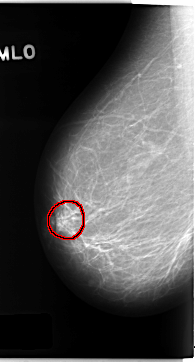

C_0155_1.RIGHT_MLO

RIGHT_MLO LINES 4696 PIXELS_PER_LINE 2528 BITS_PER_PIXEL 12 RESOLUTION 50 OVERLAY

FILE: C_0155_1.RIGHT_MLO.OVERLAY

TOTAL_ABNORMALITIES 1

ABNORMALITY 1

LESION_TYPE MASS SHAPE LOBULATED MARGINS ILL_DEFINED

ASSESSMENT 5

SUBTLETY 4

PATHOLOGY MALIGNANT

TOTAL_OUTLINES 1

BOUNDARY